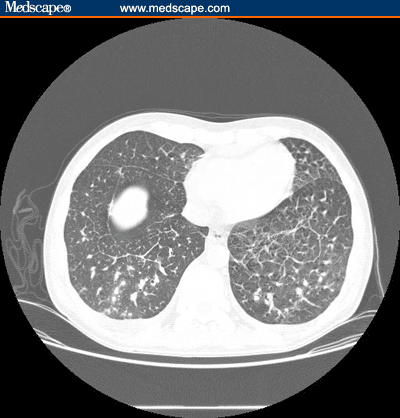

The patient returned to clinic 4 weeks later with a 1-week history of fever, dyspnea on exertion, cough, and diarrhea. The patient was febrile with a temperature of 38.3° C. There were several new cutaneous lesions and the palatal lesion had increased to 3 x 4 cm2. The plasma HIV-1 RNA level had decreased to 800 copies/mL and the CD4+ cell count increased to 320 cells/mcL. A chest radiograph and CT scan were performed (Figures 2a and 2b).

Figure 2a.

Chest radiograph of HIV-infected man with Kaposi's sarcoma.